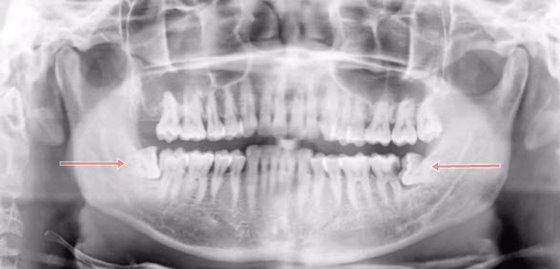

ฟันอีก 4 ซี่ที่เหลือ ก็คือ ฟันกรามซี่ที่ 3 ทั้งบน-ล่าง-ซ้าย-ขวานั่นเอง ฟันกรามเจ้ากรรม 4 ซี่นี้ จะฝังอยู่ในกระดูกขากรรไกรใต้เหงือก ซึ่งฟันคุดในบางรายอาจจะไม่ปวดเพราะมันนอนนิ่งอยู่เฉยๆ แต่ในขณะที่คนส่วนใหญ่ ฟันกรามซี่ที่สามจะพยายามงอกขึ้นมาให้ได้ แต่ขากรรไกรก็มีพื้นที่อยู่จำกัด ไม่พอให้ใครมาแทรกได้แล้ว ฟันจึงค่อยๆ เอียงและไปชนกับฟันกรามซี่ที่สองที่อยู่ข้างๆ ทำให้เกิดการอักเสบ บวม หรืออาจมีการติดเชื้อร่วมด้วย สิ่งที่เกิดขึ้นทั้งหมดนี้ ถ้าน้องๆ ส่องกระจกก็จะเห็นแค่เหงือกบวมๆ เท่านั้นเอง แต่ไม่รู้หรอกว่าภายใต้เหงือกของเราเกิดอะไรขึ้นบ้าง จนกว่าจะได้ไปเอ็กซเรย์ช่องปาก พี่มิ้นท์เชื่อว่าหลายคนที่เกิดอาการฟันคุดและได้เห็นฟิล์มเอ็กซเรย์ช่องปากของตัวเอง ที่มีฟันคุดนอนแอ้งแม้งสบายใจอยู่ในสุด คงอุทานกันหนักมากเลยล่ะค่ะ